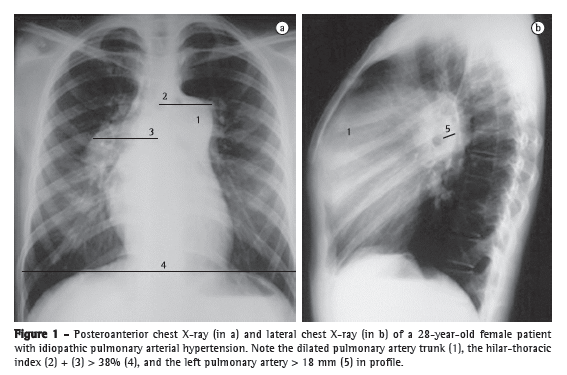

Chest X-ray changes are seen in more than 85% of patients with a confirmed diagnosis of PH.(4) The major changes found include increased pulmonary artery diameter at the hilar level, in 78% of cases (Figure 1); peripheral tapering of vessels, in 62%; and hyperlucent lung periphery, in 9% (Figure 2). The pulmonary artery diameter at the hilar level can be determined by measuring the interlobar artery diameter. The maximum transverse diameter of the right interlobar artery, as measured from its lateral aspect to the air column of the intermediate bronchus, is 16 mm in men and 15 mm in women.(5) Because of the difficulty in assessing the left pulmonary artery by posteroanterior chest X-ray, the vessel should be assessed by lateral X-ray, beginning at the circular transparency created by the left upper lobe bronchus (which is visualized as being telescoped) and extending to the posterior margin of the vessel saddling the bronchus (Figure 1). The maximum limit of normality is 18 mm. A hilar-thoracic index (sum of the diameters of the pulmonary hila divided by that of the chest) above 38% is classically described, being present in approximately 75% of patients with PH (Figure 1).(6) Vascular calcification, usually located in the pulmonary artery trunk (PAT) or in its hilar branches, is rarely detected. This change is most commonly associated with congenital heart diseases and chronic central embolism.